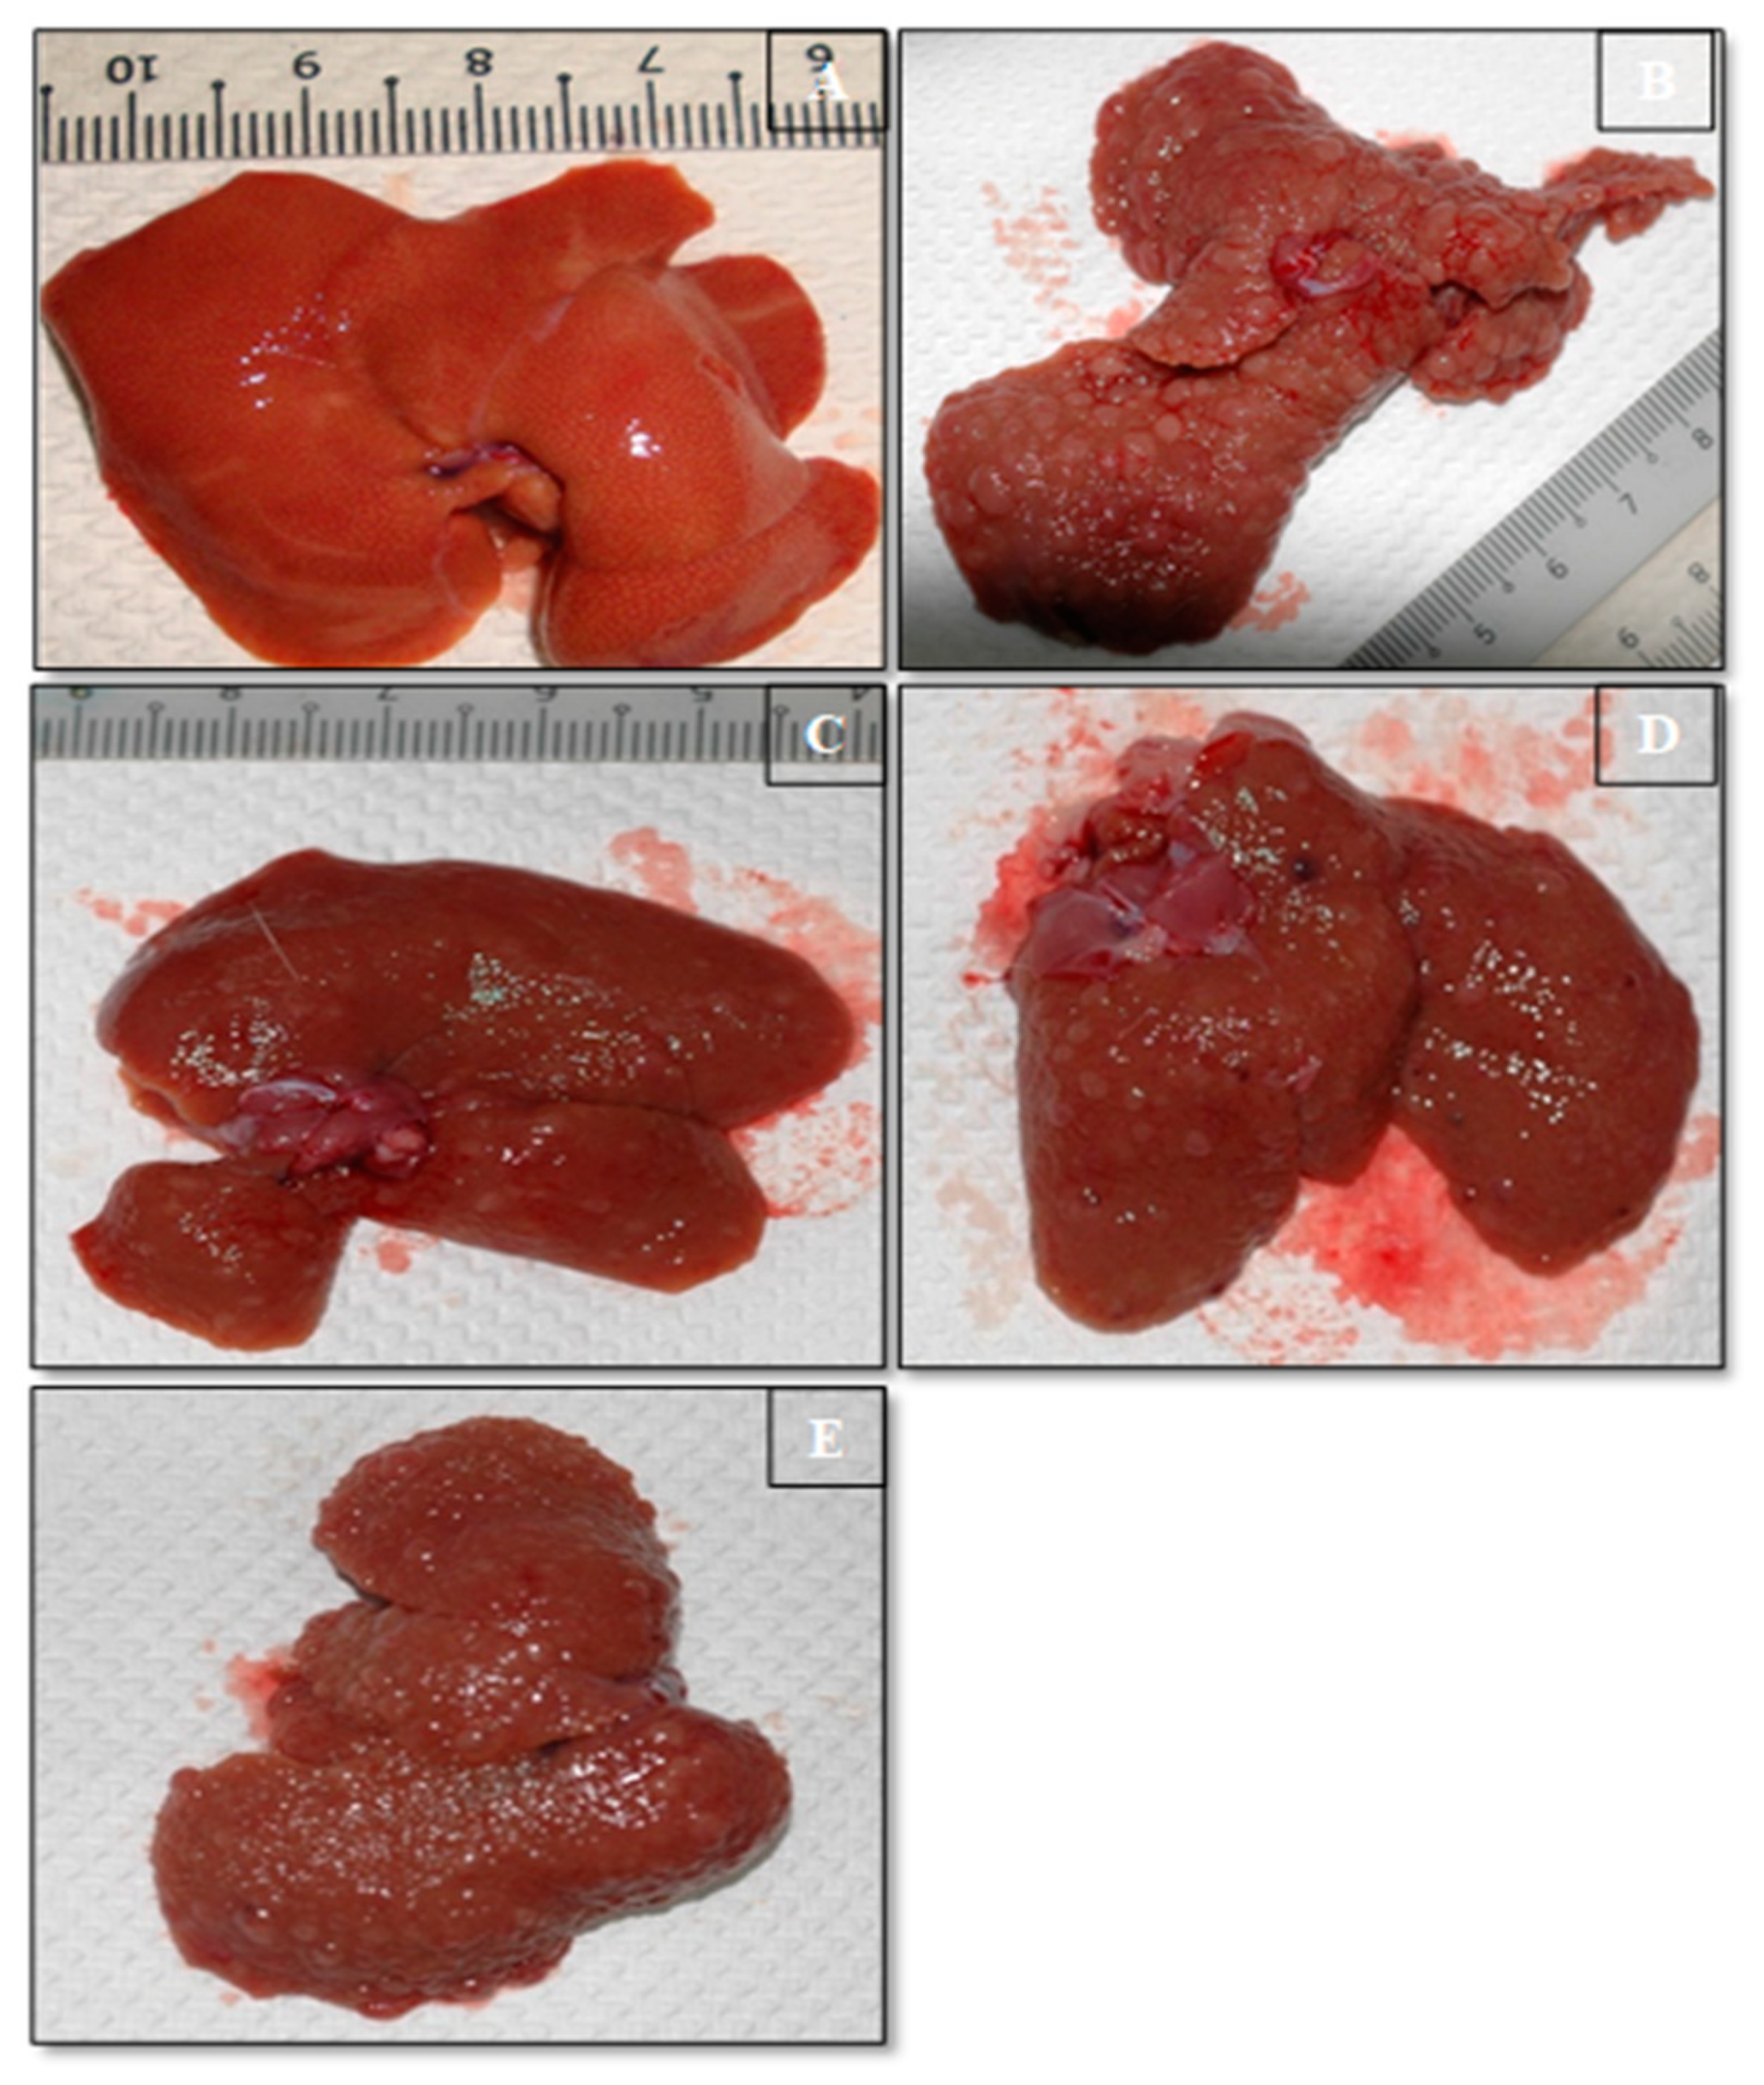

3.5. Morphology of Liver